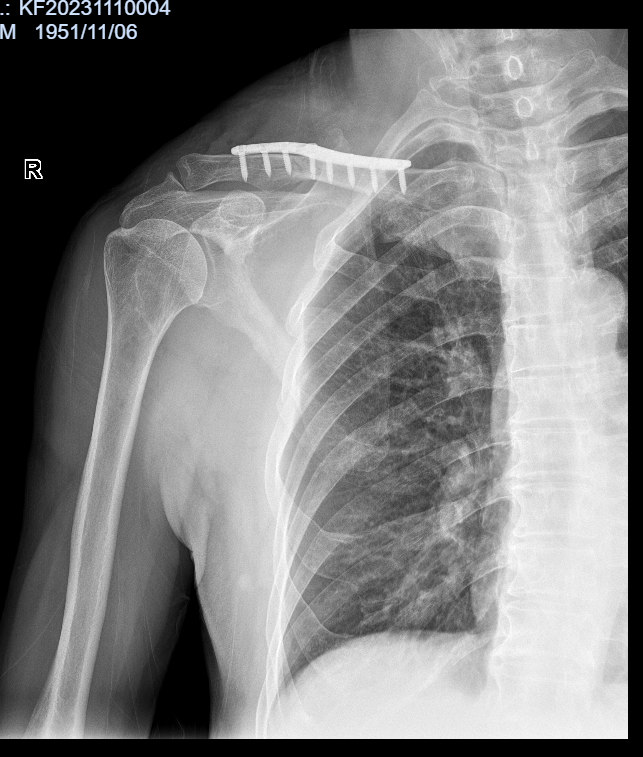

病例六:患者,男,71岁,因“摔伤致右肩部疼痛伴活动受限1小时余”入院。诊断:右锁骨骨折;行右锁骨骨折切开复位内固定术;手术顺利,术后恢复良好,顺利出院。

右锁骨骨折 术前X线片 右锁骨骨折 术前三维CT

右锁骨骨折 术后X线片